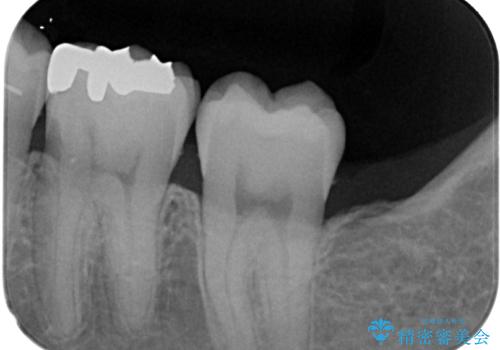

- セラミックにやり替えたいとのことで来院された患者様です。検査の結果、レントゲン上でメタルインレーの不適合を認めたのでセラミックインレーによる修復治療を行っていくことにしました。

拡大鏡視野下で、メタルインレー、虫歯の除去を行い、セラミックインレーに適した形に整えました。